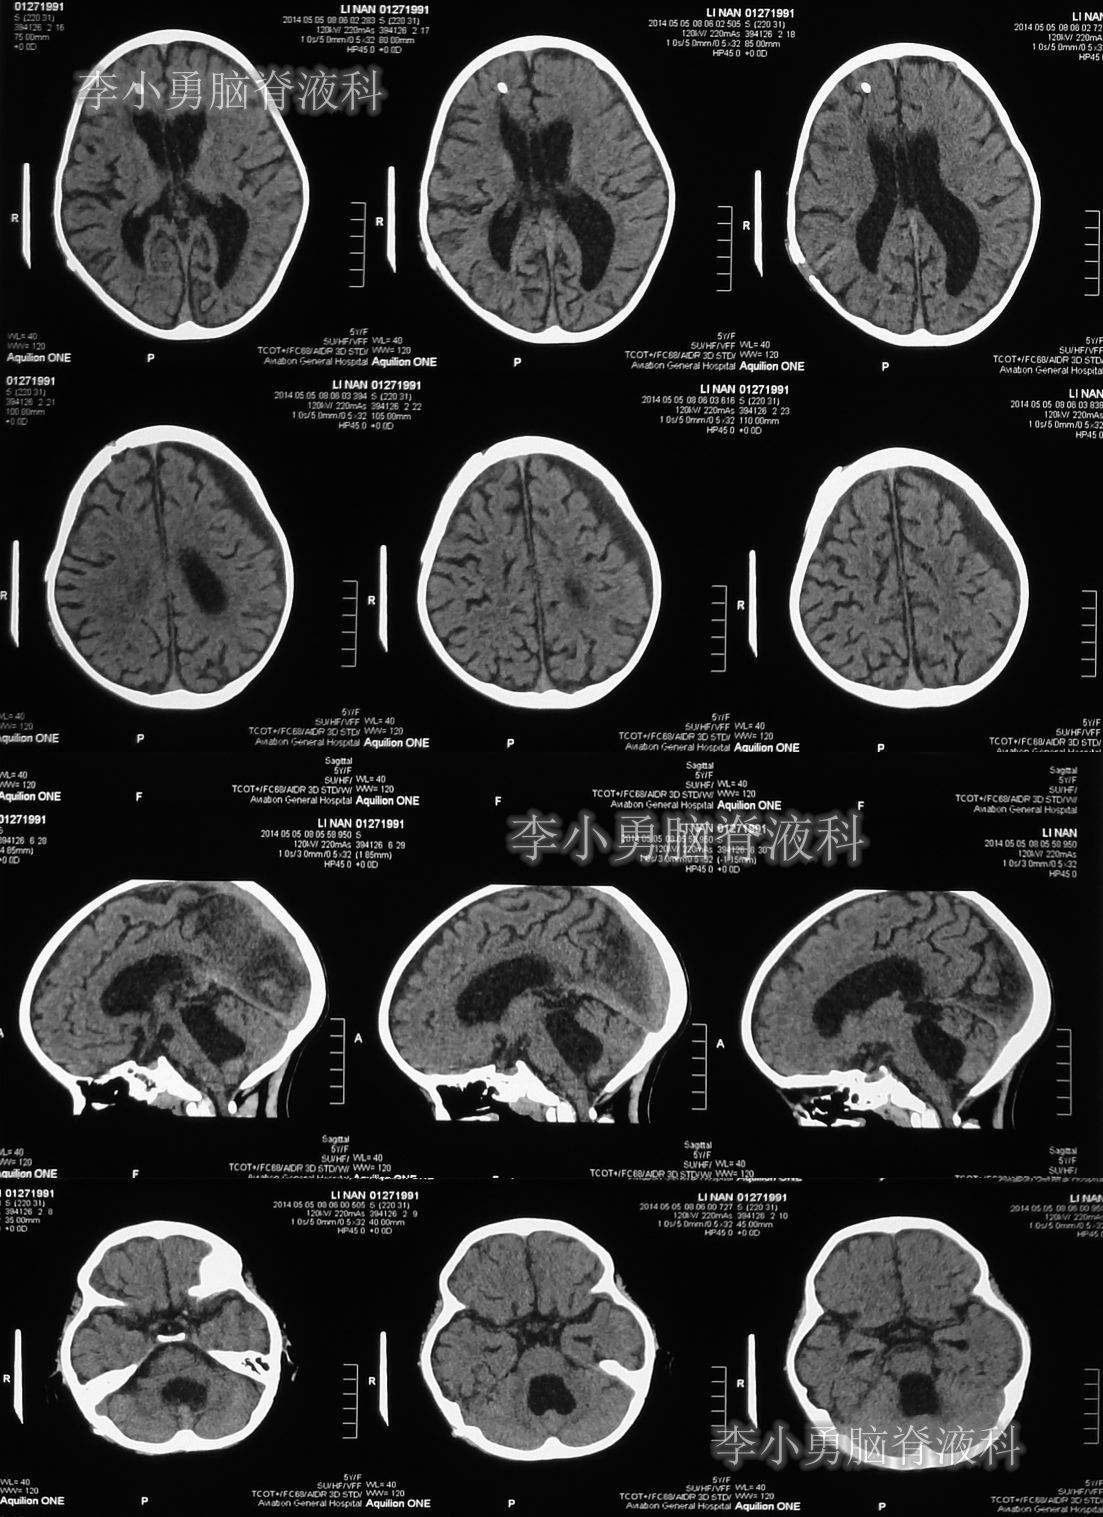

图-14:2014年5月5日术后当天头颅CT

脑室腹腔分流术后次日早晨即住院第51天或2014年5月6日,患儿出现了嗜睡,精神变差,表情痛苦及呕吐的表现(图-15)。

当天头颅CT示第四脑室及脑室系统又有明显扩张(图-16);CT检查后,床旁急行左额角脑室外引流术。

图-16:2014年5月6日头颅CT

脑室外引流术后第2天即2014年5月7日,复查头颅CT示脑室系统仍扩张,分流管脑室端游走脱位(图-18)。

图-18:2014年5月7日头颅CT

脑室外引流术后第3天即2014年5月8日,接受了脑室腹腔分流脑室端调整术;术后当日查头颅CT示脑室系统扩张减轻(图-19)。

图-19:2014年5月8日头颅CT